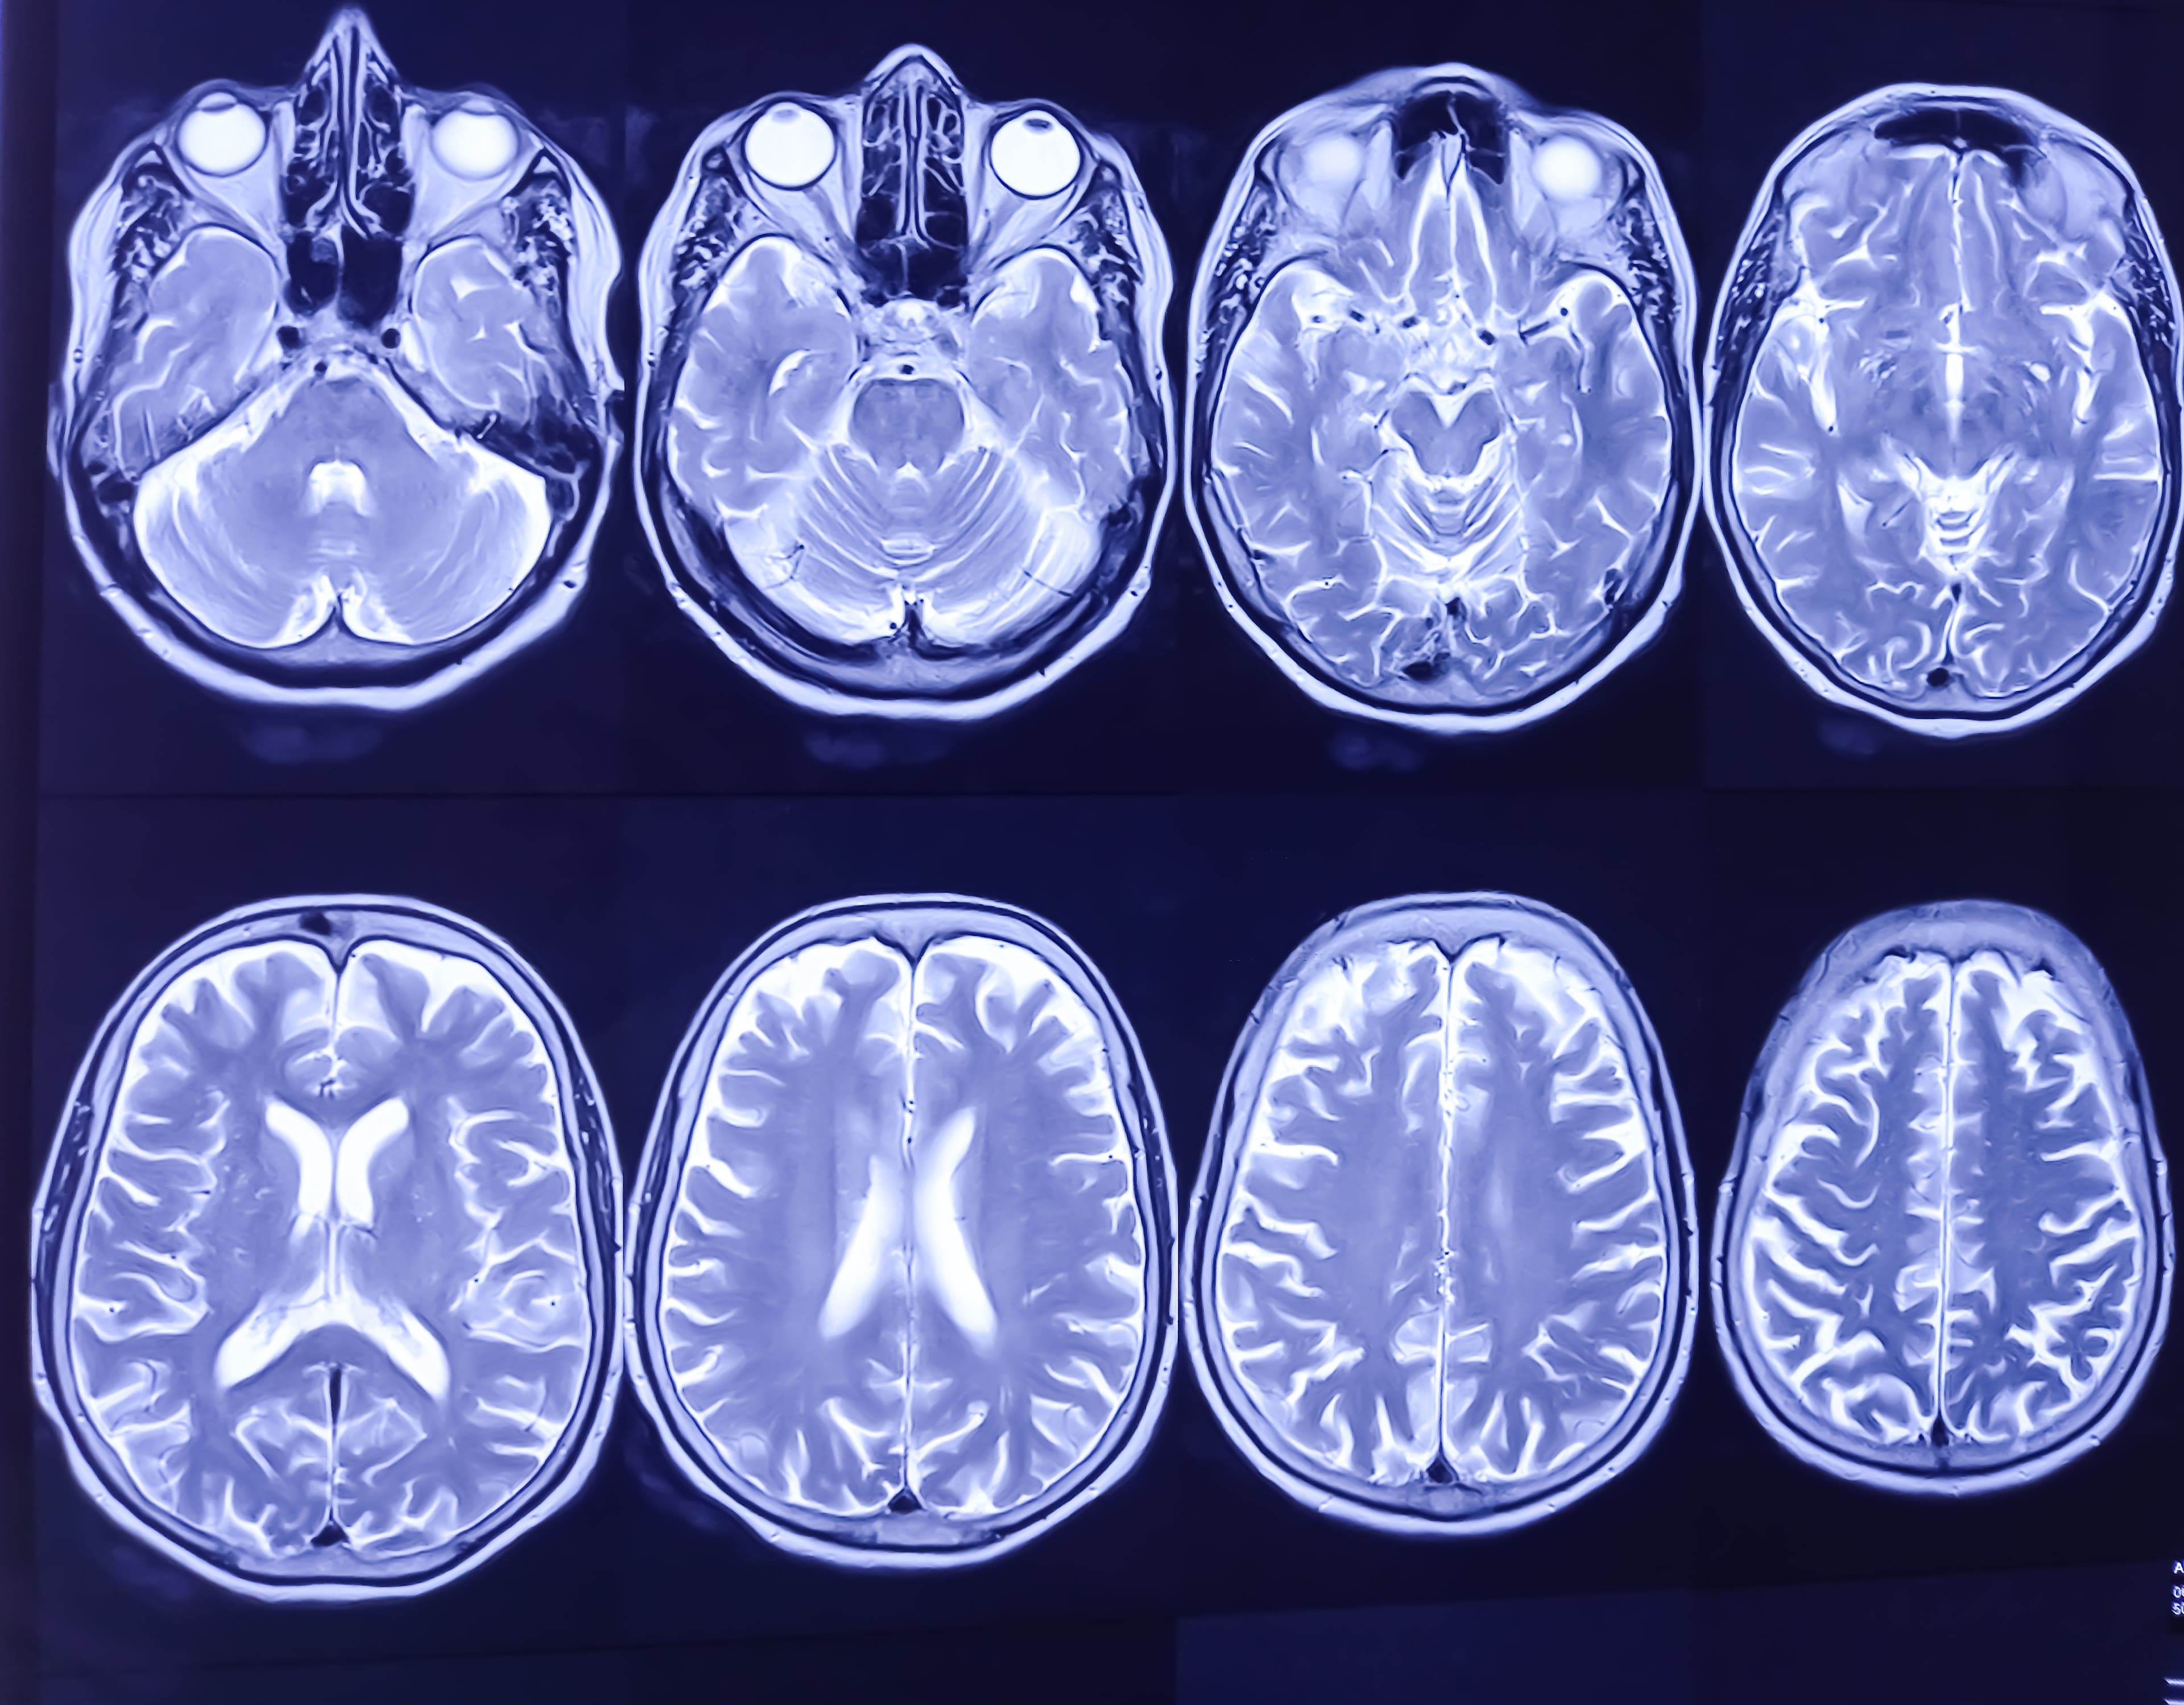

As brain injury and neurological conditions become more prevalent, the need for advanced imaging technology has never been greater. Brain Mapping Solutions is leading the way with cutting-edge MRI/DTI post-processing software that provides clear, accurate images of the brain, helping doctors make more informed decisions about treatment.

With a commitment to innovation, Brain Mapping Solutions continues to enhance its software to meet the evolving needs of healthcare providers. Their advanced imaging tools help doctors diagnose and treat brain injuries more effectively, providing patients with better care and improving long-term outcomes.

Brain Mapping Solutions offers PRISM Imaging, a state-of-the-art neuroimaging tool that enhances the detection of traumatic brain injuries, seizures, CNS neoplasms, and neurodegenerative diseases.